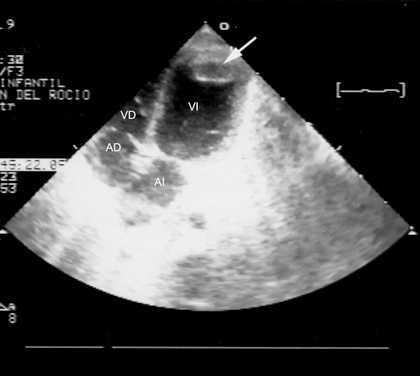

Con 19 días de vida se objetivó una ectasia coronaria izquierda cuyo calibre era de 4 mm (> 3 DS; fig. 3) instaurándose tratamiento con gammaglobulina i.v. (2 g/kg/24 h), repetida en un segundo ciclo a la semana del primero, y aspirina (40 mg/kg/día 2 semanas, pasando a 5 mg/kg/día durante 3 meses).

Figura 3. Dilatación de la arteria coronaria izquierda (19 días de vida): ecocardiografía 2D, proyección paraesternal del eje corto inmediatamente por encima de la válvula aórtica. Obsérvese que la dilatación es exclusiva del tronco común de la arteria coronaria izquierda después de su bifurcación, el calibre de la arteria descendente anterior y circunfleja es normal.